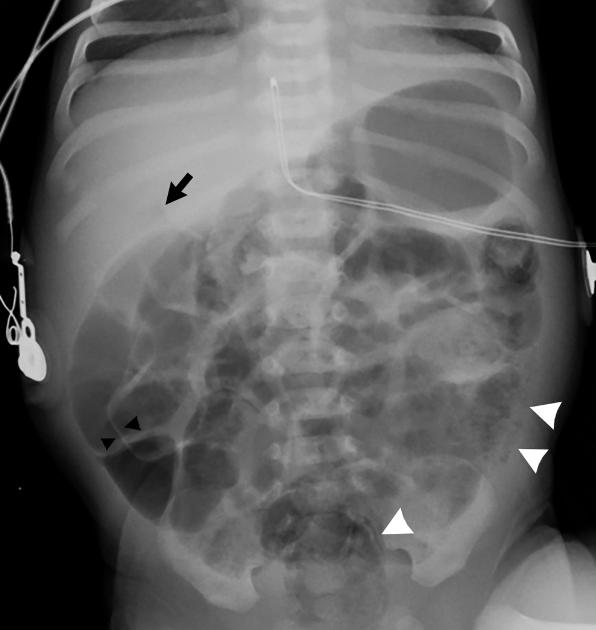

what does a football sign mean on XR?

Seen with massive pneumoperitoneum

In supine position air collects anterior to abdominal viscera

pneumoperitoneum